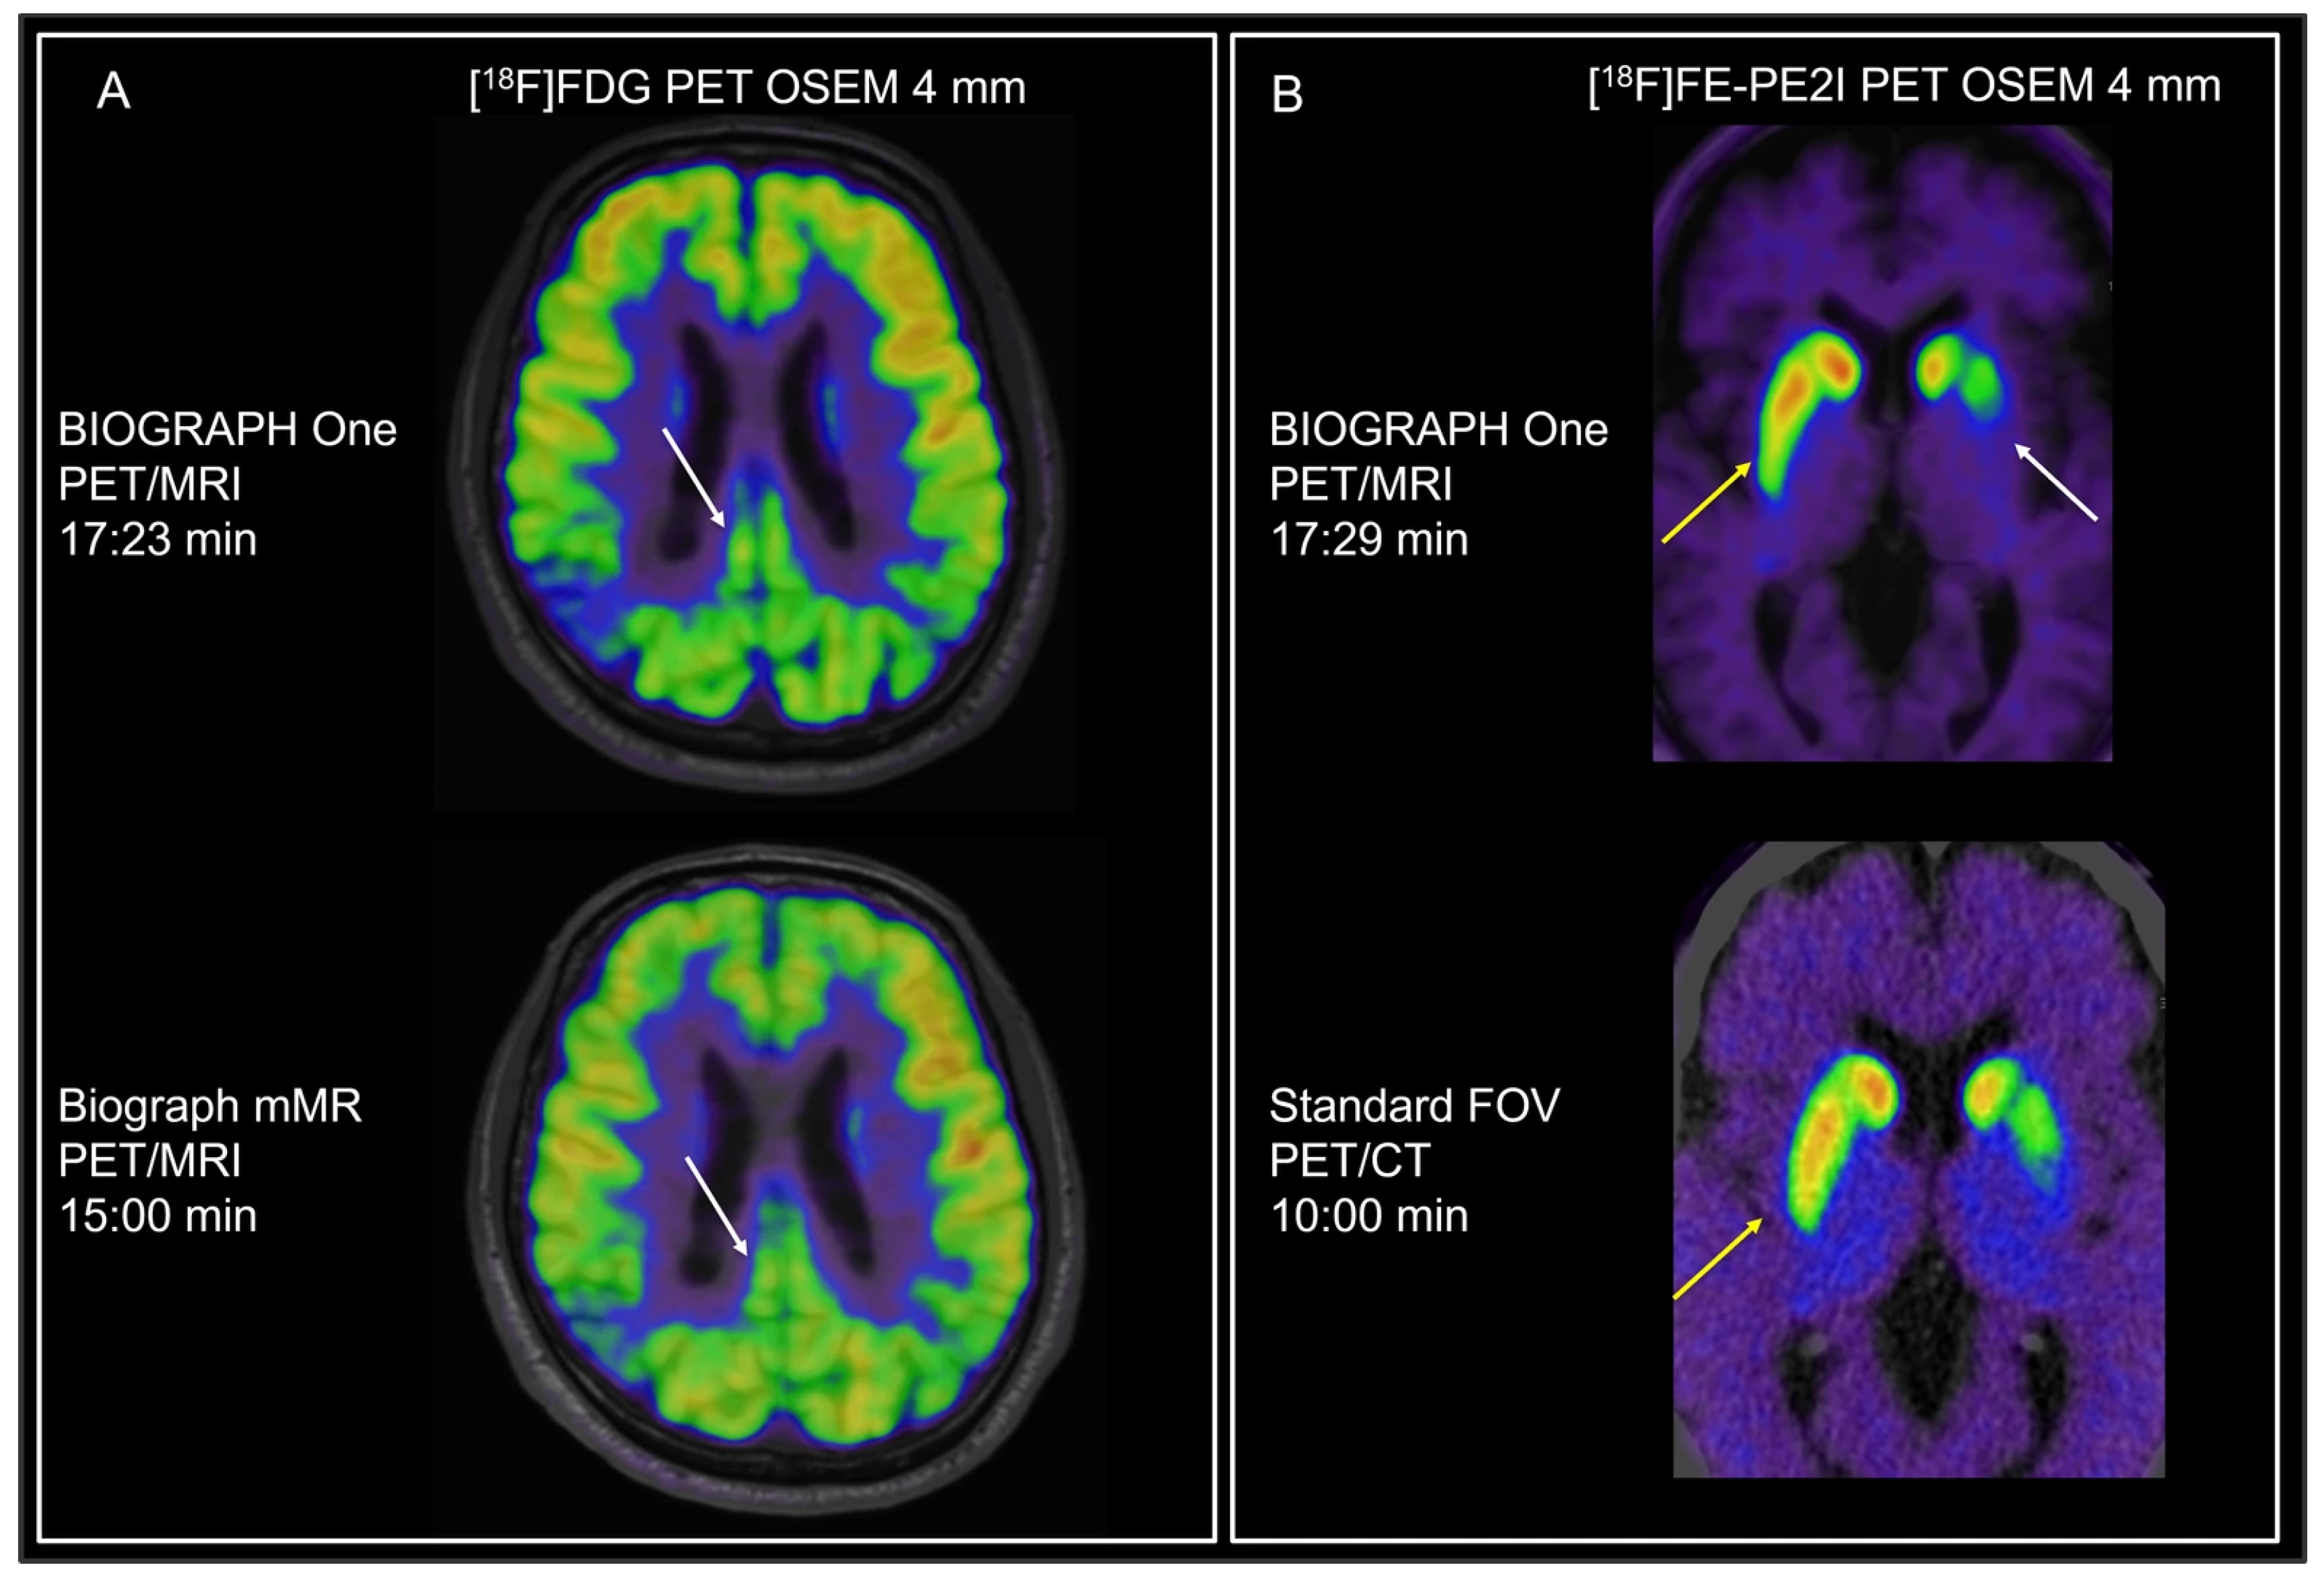

| Brain neuro [18F]FDG | 200 MBq 40 min p.i. | OSEM + TOF 4 mm Gauss 12 iterations/5 subsets | - | 15 min OSEM 4 mm Gauss 4 iterations /21 subsets | 10:00/17:26 min b OSEM + TOF 4 mm Gauss 12 iterations/5 subsets |

| Brain neuro [18F]FE-PE2I | 200 MBq 30 min p.i. | 10 min OSEM + TOF 4 mm Gauss 12 iterations/5 subsets | - | 10 min PSF 4 mm Gauss 4 iterations/21 subsets | 10:00/18:07 min b OSEM + TOF 4 mm Gauss 12 iterations/5 subsets |

| Brain neuro ([18F]FDG) | 34.20 | 22:49 | 1.6 [1.6;1.6] | 2.9 [2.7;2.9] | 3 [2.5;3] |

| Brain neuro ([18F]PE2I) | 40:53 | 24:02 | 1.7 [1.6;1.8] | 2.6 [2.6;2.8] | 3 [3;3] |

| COV WM (%) | 9.6 [9;11.5] | 11.7 [10.9;16.0] | 10.7 | - |

| SUVr Frontal | 1.22 [1.19;1.38] | 1.06 [0.96;1.20] | 1.21 | - |

| SUVr Occipital | 1.34 [1.18;1.45] | 1.13 [1.08;1.41] | 1.26 | - |

| SUVr Striate | 1.38 [1.24;1.49] | 1.22 [1.10;1.36] | 1.28 | - |

4.3. Brain Applications